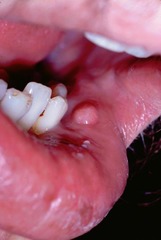

pustules ( Clinical Appearance of Soft Tissue Lesions)

Front

Variously sized circumscribed elevations containing pus.